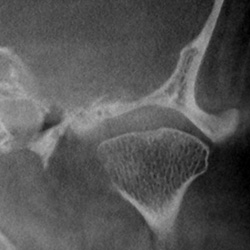

• Knöcherne Erkrankungen des Kiefergelenks

• Ausschluss primärer Kiefergelenkerkrankungen

Präimplantäre Diagnostik OberkieferSinusbogenaugmentationKiefergelenk